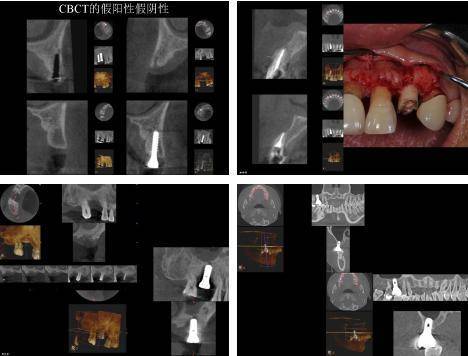

У области оралне имплантације, ЦБЦТ је постигао добре резултате у дизајнирању хируршких планова, симулацији имплантата и изради хируршких водича.

Подаци добијени ЦБЦТ-ом се увозе у софтвер за виртуелно пројектовање имплантата треће стране, који може да увезе ЦТ податке вилица за 3Д реконструкцију и реконструише комплетну анатомију вилице сваког пацијента. Клиничар може користити софтвер да јасно прикаже специфичну морфологију анатомије вилице у сагиталној, короналној и попречној равни, посматра положај симулиране локације имплантата у односу на суседне важне анатомске структуре, избегава важне анатомске структуре, смањује ризик од операције и дизајнирати симулирани хируршки план.